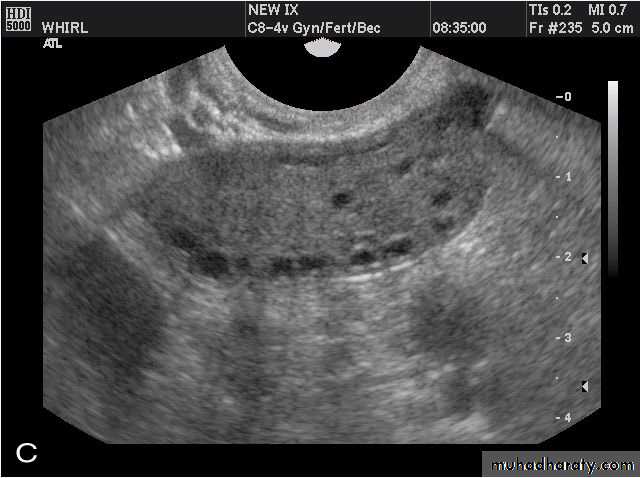

POLYCYSTIC OVARY SYNDROME

Images from women with differing expressions of the four major subtypes of the metabolic syndrome associated with polycystic ovary syndrome (A–D). The images exhibit quite differing ultrasonographic appearances in the size and distribution of follicles within PCOS ovaries. A recent corpus luteum is clearly visible in the ovary in panel (D).

• POLYCYSTIC OVARY SYNDROME

Images from women with differing expressions of the four major subtypes of the metabolic syndrome associated with polycystic ovary syndrome (A–D). The images exhibit quite differing ultrasonographic appearances in the size and distribution of follicles within PCOS ovaries. A recent corpus luteum is clearly visible in the ovary in panel (D).• POLYCYSTIC OVARY SYNDROME

Images from women with differing expressions of the four major subtypes of the metabolic syndrome associated with polycystic ovary syndrome (A–D). The images exhibit quite differing ultrasonographic appearances in the size and distribution of follicles within PCOS ovaries. A recent corpus luteum is clearly visible in the ovary in panel (D).The Oviduct (Fallopian Tube)